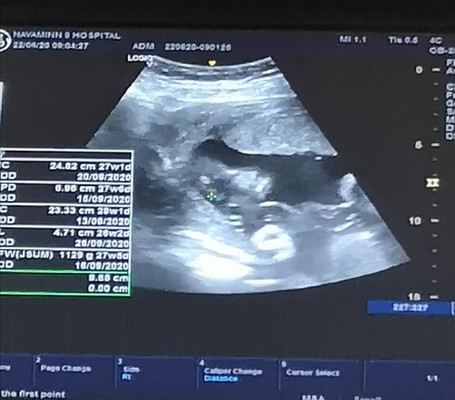

ลูกหมู27week

น้ำนักตอนนี้1120กรัม ปกติอายุครรภ์27week น้ำหนักจะอยั่700-800กรัม